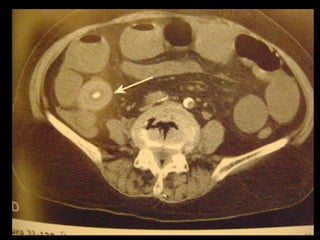

Vesícula Biliar Errante

A vesícula biliar pode ter um mesentério longo que

lhe permite migrar até uma posição anômala,

como a pelve é a chamada vesícula biliar

flutuante ou errante;

Pode migrar para a frente da coluna vertebral ou

para a esquerda do abdômen e, em raros casos,

herniar para a bolsa omental;

Estão sujeitas a torção e volvo.